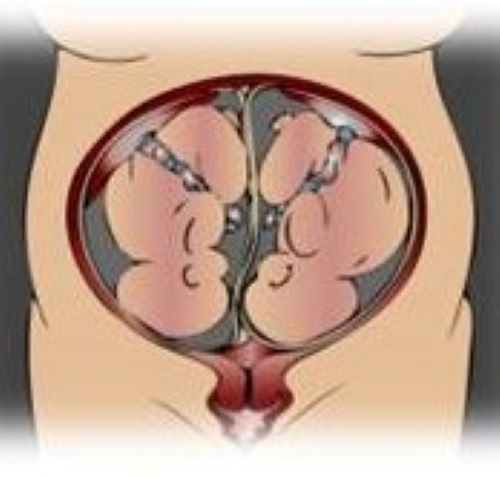

Maternal Fetal Medicine →

The mission of the Maternal Fetal Medicine Fellowship Program is to educate and train fellows to deliver high quality, prompt and compassionate care to the diverse population of women with high-risk pregnancies and certain medical conditions in Central Massachusetts. Our division is devoted to training fellows in a supportive and collegial environment to prepare the next generation of well-rounded clinicians, educators, researchers and leaders in the field.

Neonatal-Perinatal Medicine →

The mission of the Neonatal-Perinatal Medicine Fellowship is to provide a supportive, scholarly and collegial environment for education and training that allows fellows to become successful academic neonatologists, with expertise in clinical neonatology, through our structured curriculum, clinical teaching and/or research.